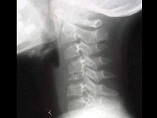

- 单项选择题男,37岁, 颈部疼痛,活动时加重, 休息可减轻,夜间有盗汗, 结合图像,最可能的诊断是 ( )

D、颈椎结核